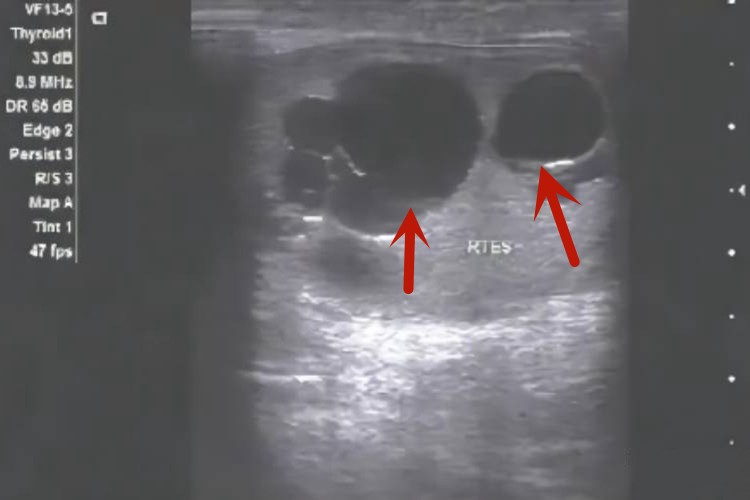

睾丸鞘膜积液的肿物位于阴囊内,一般无自觉症状,表现为阴囊增大,呈卵圆形或梨形,睾丸附睾触摸不清,积液较多时会出现囊肿,还会有阴囊下坠感或轻度的牵扯痛。

精液囊肿会在睾丸或附睾部触到边缘光滑,质软而有囊性感的圆形肿块,小囊肿刚可扪及,大囊肿可达鸡蛋大小,酷似睾丸,多发于附睾头部,囊肿透光试验阳性。